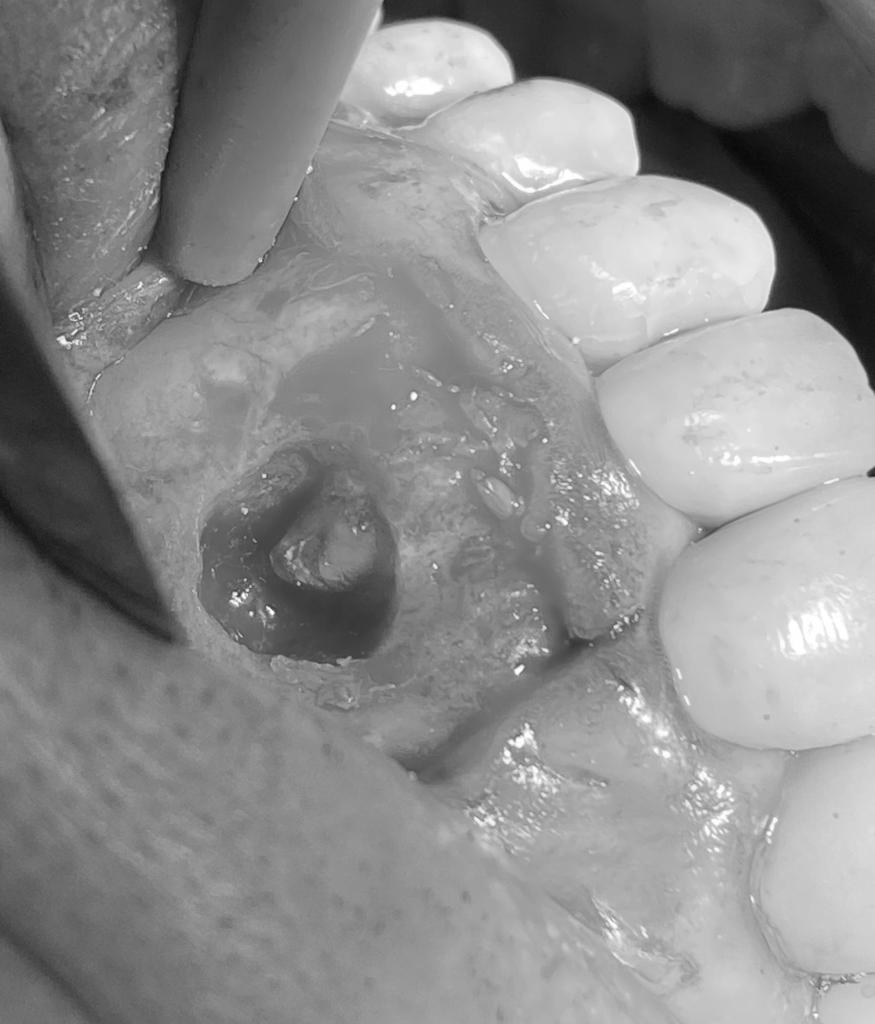

Cirurgia Endodôntica

Em determinadas situações em que o retratamento endodôntico não foi bem-sucedido ou que não foi possível ser realizado, a cirurgia endodôntica surge como uma alternativa para a manutenção do dente em função. Consiste no acesso cirúrgico à região apical da raiz (ponta da raiz), curetagem do tecido inflamatório e selamento do canal a partir da raiz.